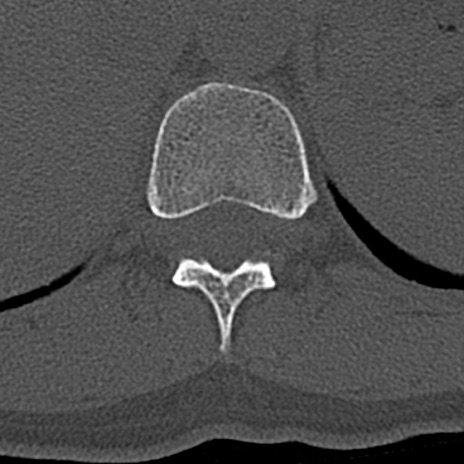

腰椎CT

横断像と矢状断像